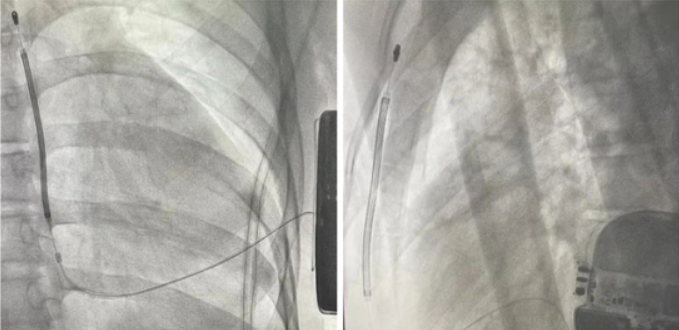

手术过程中,团队配合默契:精确规划电极和装置放置位置,避开透析通路;麻醉监护:行胸椎神经阻滞,全程严密监测生命体征,确保手术安全;精准植入:在左侧胸壁制作皮下隧道,放置电极和脉冲发生器;系统测试:诱发性室颤,确认S-ICD能准确识别并有效除颤。在皮林主任的指导下,心外科副主任医师伍光、心内科主治医师刘滕飞参与手术。手术历时约一小时,过程顺利。患者术后恢复良好,次日即可下床活动。出院时,患者感慨道:“以前总觉得自己揣着个‘定时炸弹’,现在终于能睡个安稳觉了。”